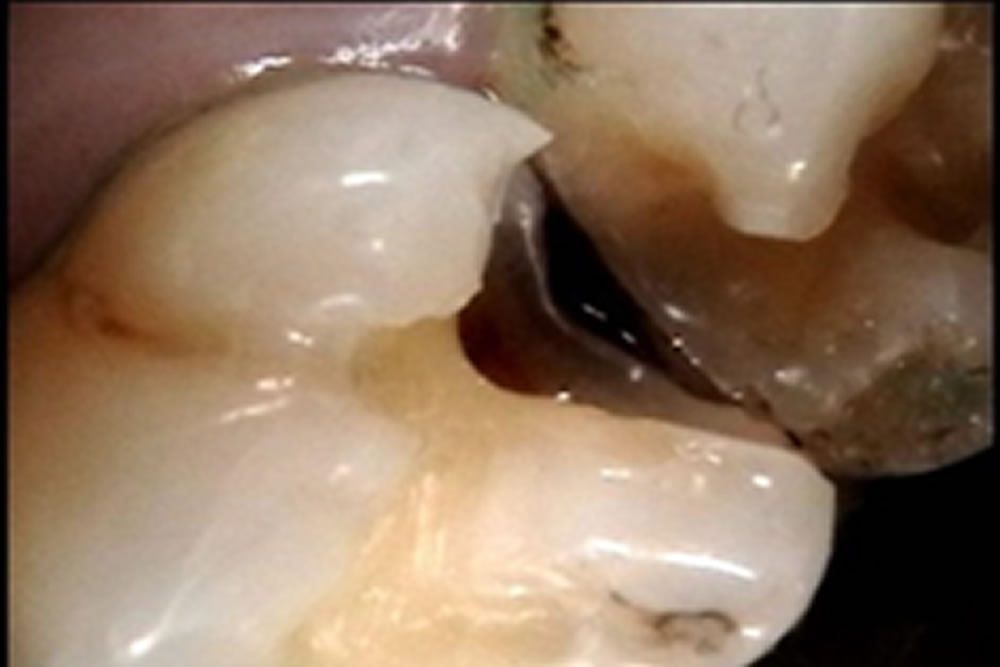

再発した虫歯を治療後にセラミックアンレーで修復した症例

再発した虫歯を治療後にセラミックアンレーで修復した症例 こちらの患者さまは検診希望にて来院されました。 口腔内とレントゲンを確認したところ、他院で治療したセラミックインレーの周りがむし歯になっていました。 セラミックイン […]